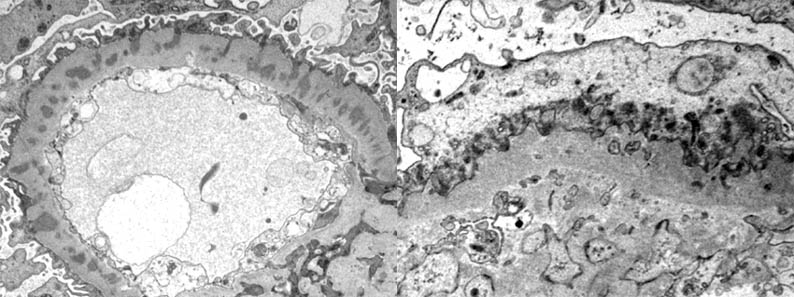

There are electron-dense deposits in the epithelial aspect (external) of the GBM, between this one and the epithelial cell: subepithelials or epimembranous. These deposits are usually diffuse and homogenously distributed, but they can be, in some cases, irregularly distributed. Spikes are demonstrated as irregular projections of the GBM among the subepithelial deposits; with progression of the disease these projections become longer and surround the deposits incorporating them in a thickened GBM. The deposits are amorphous; the presence of organized deposits must alert of a possible lupus nephritis. These deposits lose their electron density until disappear in the advanced stages of the process. Like in many other diseases with NS, there is a variable loss or effacement of podocyte foot processes. In some cases, more frequently secondary, there are dense deposits in mesangium. (Image of MGN stage II (link) - More EM images (link)

Figure 12a. Left: electron-dense deposits on the outside of the basement membrane, without reaction of this around the deposits: Stage I. Right: deposits surrounded laterally by material similar to that of the basement membrane ("spikes"): Stage II. Original magnification, X4,000. (Images courtesy of Dr. Carlos A, Jiménez).

Figure 12b. Left: Electron-dense deposits are completely surrounded by basement membrane-like material, giving the appearance of being "embedded" within a very thick and irregular basement membrane: Stage III. Right: the glomerular basement membrane is thick and irregular and electron-dense deposits have almost disappeared: Stage IV. Original magnification: left, X4,000, right, X6,000. (Images courtesy of Dr. Carlos A, Jiménez). Note the extensive loss of pedicels in the four previous images.